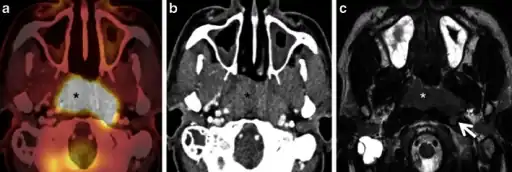

a) Axial PET/CT image reveals a FDG-avid mass in the nasopharynx in keeping with a known nasopharyngeal carcinoma b)axial CECT image shows the infiltrative nasopharyngeal carcinoma c) axial T2W MR image demonstrates the infiltrative nasopharyngeal carcinoma